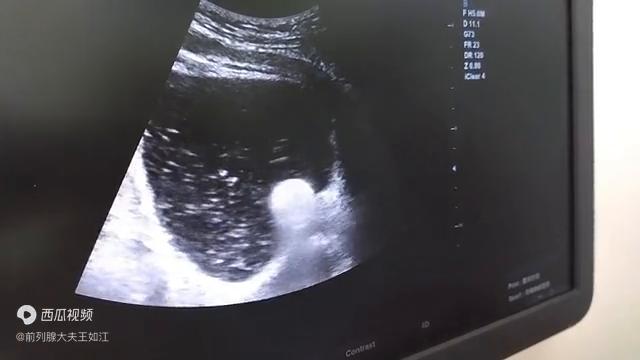

具体就像图上所演示的。我们先把这个尿管。

·水囊那一段先拉到尿道里面,拉到钙化灶卡压的下方。然后开始把水囊打起来。随着水囊的扩张,它把钙化灶包绕尿道给它整个扩开。水囊的压力在尿道盛不下的时候,它要往膀胱里面去运动。这个时候把膀胱颈口、尿道内口那个地方又进行水囊强力的撑开。

·一般撑开的时候,这个时候水囊大小大概在6-8毫米,充分的就把尿道内口也打开了。也就是说疏通术是把淤堵到尿道里面的,已经被消融的钙化灶捅出来。扩张术,它是把被钙化灶所包绕的尿道和被尿道卡压的尿道内口和膀胱颈口这个位置,给它用水囊扩开,达到一个解除尿路梗阻,消除尿路刺激的这么一个症状。

刚才这个图大家看都很清楚,大量的白色絮状物,斑片状的物质,而且清晰地看到了尿道内口被水囊扩开的一个过程。这个尿道扩张疏通术,它只是用的最简单的一些普通导尿管,巧妙的用了它水囊的这种柔软的,无创的扩张作用。起到了这个效果。